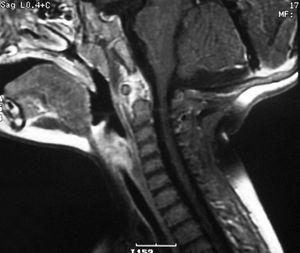

Ingresó con el mismo tratamiento y collarín cervical por mantener la sospecha de origen muscular de su tortícolis. Se realizaron varias pruebas complementarias como TC craneal, gammagrafía ósea y ecografía cervical con el objetivo de detectar, entre otros procesos, tumores intracraneales, osteomielitis y masas cervicales, que terminaron por descartarse. Posteriormente se realizó una RM craneal y cervical, presentando un proceso inflamatorio a nivel atlantoaxoideo y periodontoideo compatible con espondilitis atloaxoidea (fig. 1). Ante un posible origen infeccioso, se inició el tratamiento antibiótico con cefotaxima y cloxacilina con mejoría clínica progresiva. Se incluyó perfil reumatológico, que fue negativo.

Figura 1.RM cervical secuencia T1 con Gadolinio. Señal hiperintensa en región atloaxoidea y periodontoidea compatible con proceso inflamatorio e hipercaptación lineal en espacio retrofaríngeo.

Se dio de alta en tratamiento con cefuroxima y RM cervical de control a los 10 días, apreciándose inflamación residual a nivel de C1 con recuperación clínica completa.